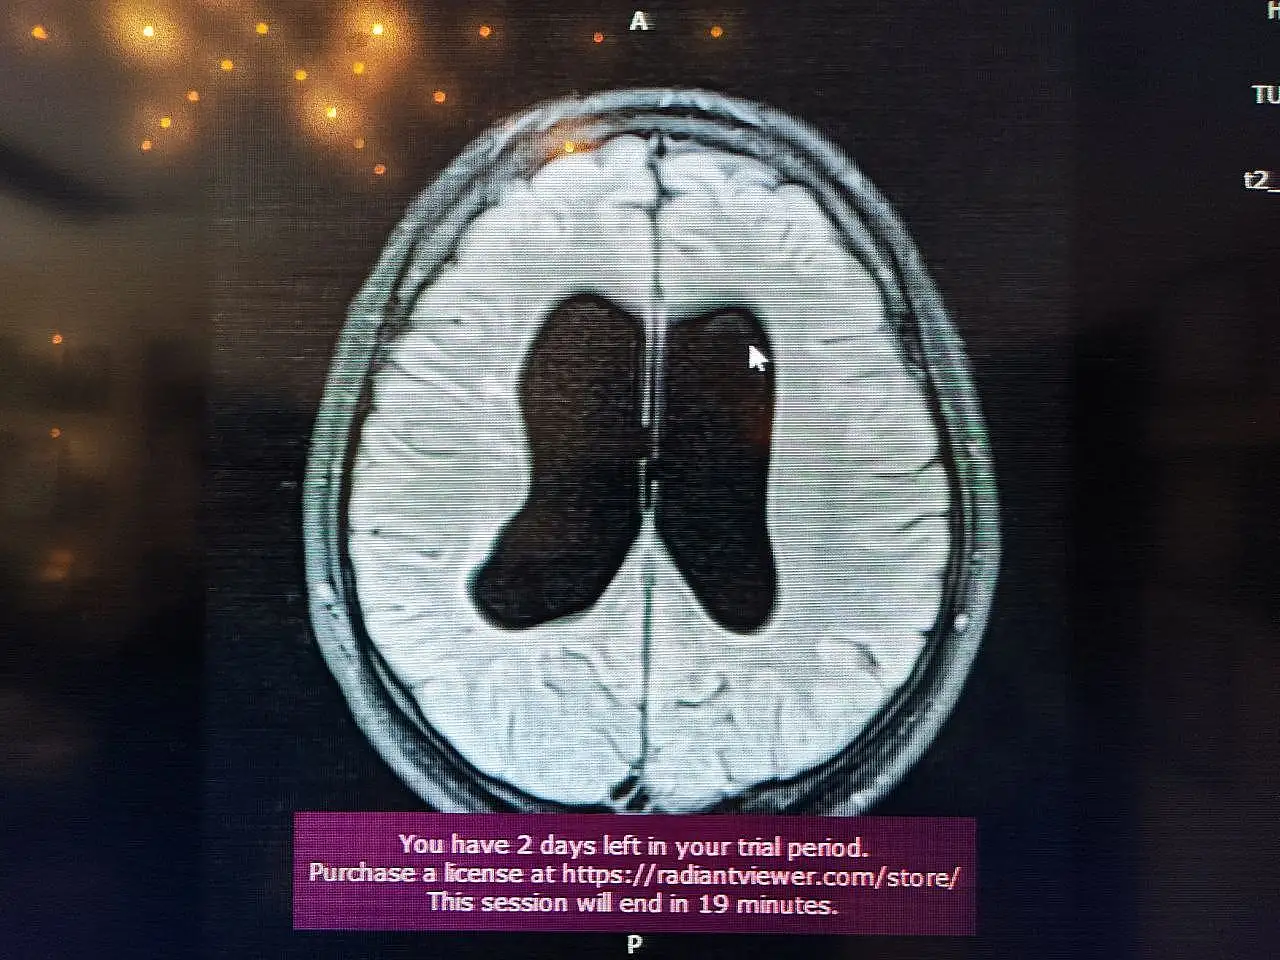

Süreçle ilgili bilgi veren Beyin, Sinir ve Omurilik Cerrahisi Uzmanı Prof. Dr. Orhan Şen, "17 yıl önce, 10 günlük bebekken annesi ve dedesi tarafından bana getirildi. Doğar doğmaz doktorlar ameliyat önermişler. Hidrosefali nedeniyle beyinde su toplanması var, bu nedenle acil ameliyat etmemiz gerekiyor yoksa ölür demişler. Gaziantep ve Adana'da farklı yerlere götürmüşler. Genel olarak hep ameliyat demişler. Ben muayenesini yaptım ve bıngıldak denilen yere baktığımda normal bombelikteydi. Anneye sordum, normal dururken kusma var mı? diye. ‘Hayır, yemek yerken kusma oluyor' dedi. Muayeneye devam ettiğimde çocuğun klinik tablosu, nörolojik muayenesi ve filmi birbiriyle uyumlu değildi. Bunun üzerine acil ameliyat gerekmiyor, izleyelim. dedim. Bıngıldakta bombe olursa ve arka arkaya kusma olursa o zaman ameliyatını yaparız dedim. Normalde ilk anne karnındayken gelişen süreçte olan bir olay. Radyolojik olarak çocuğun doğar doğmaz bu bulguyu görmemiz, hepsinin aktif hidrosefali olduğu anlamına gelmiyor. Bazen yeni doğanlarda olan ufak kanamalardan kaynaklanabiliyor" dedi.

Sözlerini sürdüren Prof.Dr. Şen "Bizim çocuğumuzda, anne karnında yaşanan bir süreç olduğu için beyine ekstra bir baskı uygulamıyordu. Beyin buna göre gelişmişti. Anne, bizim söylediğimizi tercih etti. O tercihin üzerine şu an 17 yıl geçti. 17 yaşında ve ilkokul ile ortaokulu birinciliklerle tamamlayan genç, şimdi de üniversiteye hazırlanıyor. Bizim burada asıl amacımız, özellikle genç meslektaşlarıma sesleniyorum:

Hidrosefali tanısı konulan her çocuk acil ameliyatlık değildir. Bazen arrest hidrosefali olabilir ve şant takmak gerekmiyor. İzlemekte fayda var. Her müdahale cerrahi müdahale değildir. Doğruyu söyleyip göstermek en güzel müdahaledir" diye konuştu.